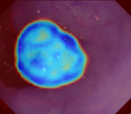

Polyps are early cancer indicators, so assessing occurrences of polyps and their removal is critical. They are observed through a colonoscopy screening procedure that generates a stream of video frames. Segmenting polyps in their natural video screening procedure has several challenges, such as the co-existence of imaging artefacts, motion blur, and floating debris. Most existing polyp segmentation algorithms are developed on curated still image datasets that do not represent real-world colonoscopy. Their performance often degrades on video data. We propose a video polyp segmentation method that performs self-supervised learning as an auxiliary task and a spatial-temporal self-attention mechanism for improved representation learning. Our end-to-end configuration and joint optimisation of losses enable the network to learn more discriminative contextual features in videos. Our experimental results demonstrate an improvement with respect to several state-of-the-art (SOTA) methods. Our ablation study also confirms that the choice of the proposed joint end-to-end training improves network accuracy by over 3% and nearly 10% on both the Dice similarity coefficient and intersection-over-union compared to the recently proposed method PNS+ and Polyp-PVT, respectively. Results on previously unseen video data indicate that the proposed method generalises.